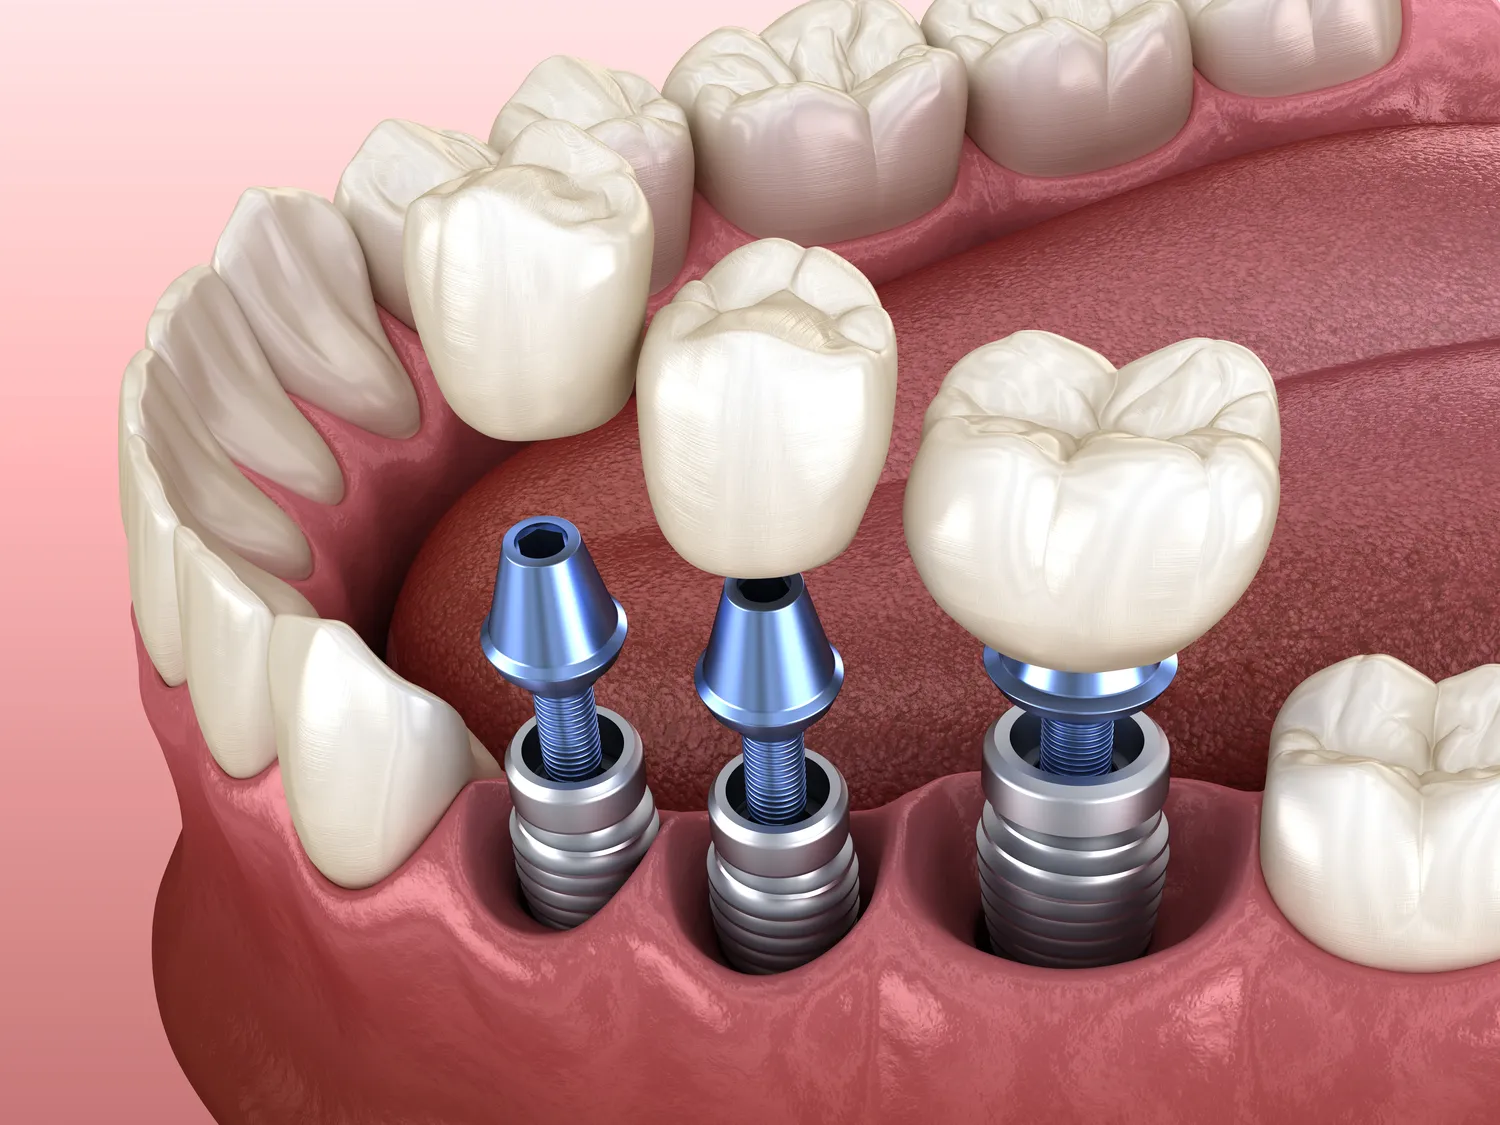

Jakie są etapy procesu wszczepiania implantów zębowych?

Proces wszczepiania implantów zębowych składa się z kilku kluczowych etapów, które są niezbędne do osiągnięcia sukcesu całego leczenia. Pierwszym krokiem jest szczegółowa konsultacja stomatologiczna, podczas której lekarz ocenia stan zdrowia pacjenta oraz wykonuje niezbędne badania diagnostyczne, takie jak zdjęcia rentgenowskie czy tomografia komputerowa. Na podstawie tych informacji lekarz podejmuje decyzję o możliwości przeprowadzenia zabiegu oraz planuje jego przebieg. Kolejnym etapem jest chirurgiczne wszczepienie implantu, które polega na umieszczeniu tytanowego słupka w kości szczęki lub żuchwy. Po tym etapie następuje okres gojenia, który trwa zazwyczaj od kilku tygodni do kilku miesięcy, w zależności od indywidualnych predyspozycji pacjenta oraz jakości kości. Po zakończeniu gojenia można przystąpić do kolejnego etapu – mocowania korony protetycznej na implancie.

Implanty zębowe i tradycyjne protezy to dwie różne metody uzupełniania braków w uzębieniu, które mają swoje zalety i wady. Implanty to stałe rozwiązanie polegające na wszczepieniu tytanowego słupka w kość szczęki lub żuchwy, co pozwala na stabilizację korony protetycznej bez konieczności szlifowania sąsiednich zębów. Dzięki temu implanty oferują lepszą estetykę oraz funkcjonalność, a także większy komfort noszenia niż tradycyjne protezy. Z drugiej strony protezy są tańszym rozwiązaniem i nie wymagają chirurgicznego zabiegu, co czyni je bardziej dostępnymi dla osób z ograniczonym budżetem lub tych, które obawiają się operacji. Jednak protezy mogą powodować dyskomfort oraz wymagać częstszego wymieniania lub regulacji ze względu na zmiany w strukturze kości szczęki.

Czas gojenia po wszczepieniu implantów zębowych jest kwestią indywidualną i może różnić się w zależności od wielu czynników. Zazwyczaj proces ten trwa od kilku tygodni do kilku miesięcy. W pierwszym etapie gojenia dochodzi do integracji implantu z kością – proces ten nosi nazwę osteointegracji i może trwać od 3 do 6 miesięcy. W tym czasie ważne jest unikanie nadmiernego obciążania implantu oraz przestrzeganie zaleceń lekarza dotyczących diety i higieny jamy ustnej. U niektórych pacjentów czas gojenia może być krótszy lub dłuższy w zależności od jakości kości oraz ogólnego stanu zdrowia organizmu. Osoby palące lub cierpiące na choroby przewlekłe mogą potrzebować więcej czasu na pełne zagojenie się tkanek wokół implantu.